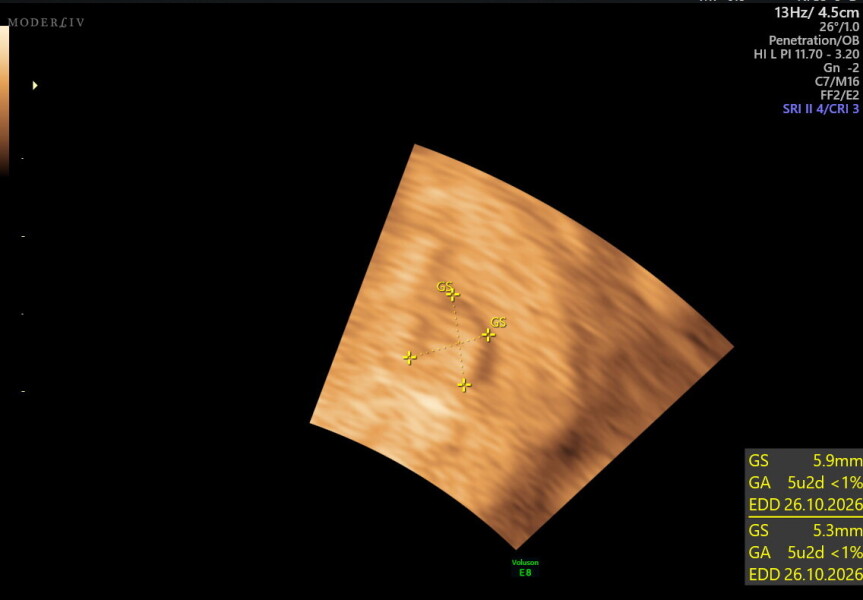

scan at 5 weeks 3 days, no heartbeats but possible twins (picture)

she then said the weird thing was that she thought she could see two sacs. she said she thought she saw it on the external scan & then on the internal when she checked. but she said it was hard to recreate the images again & then one was too blurry to see anything. from what she could measure on one it measured as 5 week2 days so pretty in line with what i thought. I have never even considered multiples, zero history in my family & I am not so old so i was shocked. she seemed very unsure but again dont know how careful she was being then said i would have to come in a weeks time, & if i needed anything in the meantime let her know

Ive attatched pictures if anyone is any good at reading, i dont feel ready to talk to anyone in real life about this yet